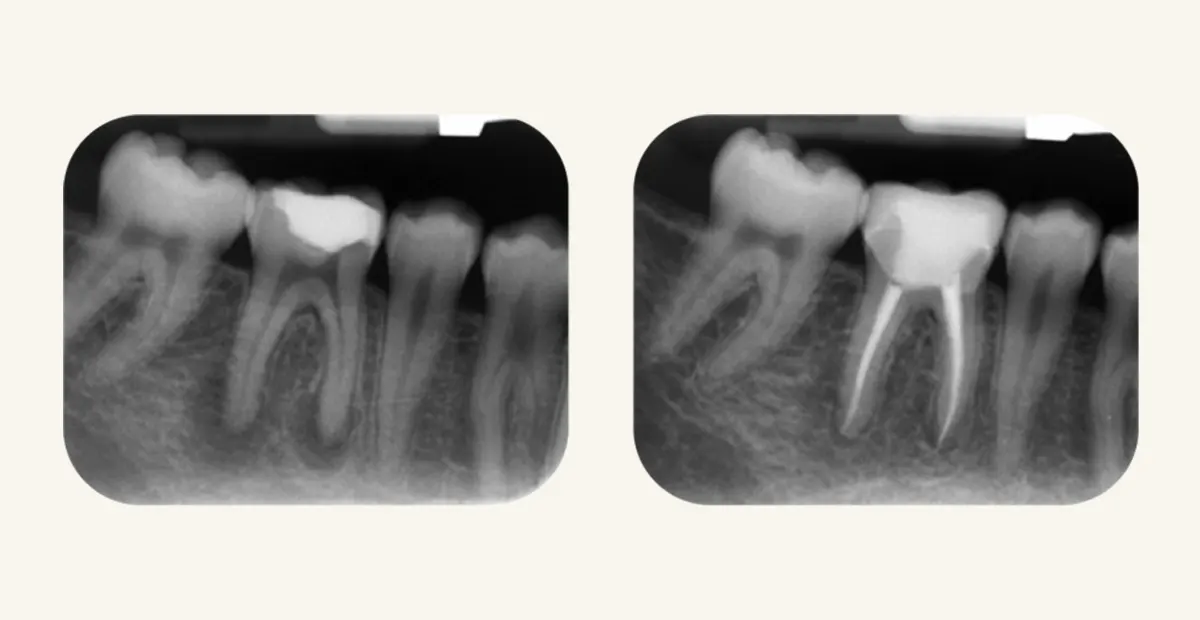

بعد از درمان ریشه که بسیاری آن را به اشتباه “عصبکشی دندان” مینامند، دندان به ترمیم نهایی نیاز دارد. نباید این ترمیم را با پر کردنی که متخصص درمان ریشه در پایان کار انجام میدهد، اشتباه گرفت. معمولاً دندانپزشکان عمومی یا متخصصان ترمیمی و زیبایی، ترمیم نهایی را انجام میدهند، نه متخصص اندو.

بیلداپ دندان یکی از محافظهکارانهترین ترمیمهای بعد از درمان ریشه است. این، در واقع باید اولین خط درمان بعد از روت کانال تراپی باشد. بیلداپ یعنی بازسازی دندان. این کار میتواند با مواد همرنگ دندان (مانند کامپوزیت) و یا مواد غیر همرنگ (مانند آمالگام) انجام شود.

در بیلداپ دندان، تا آنجا که ممکن است هیچ آسیبی به دندان درمان ریشه شده وارد نمیشود، و تنها با کمک نسج باقیمانده، مواد ترمیمی به دندان گیر داده میشوند. متخصص ترمیمی و زیبایی در این درمان، دندان را به شکل هنرمندانهای کاملاً مشابه و هماهنگ با سایر دندانهای دیگر ترمیم میکند.

پست و کور

گاهی ساختار باقیمانده دندان آنقدر کم است که مواد ترمیمی به تنهایی نمیتوانند نگهدارنده خوبی باشند. در این شرایط، دندانپزشک ممکن است از «پست و کور» استفاده کند؛ یعنی پایهای کوچک (پست) درون کانال دندان قرار داده میشود تا بازسازی (کور) روی آن شکل بگیرد.

البته این روش همیشه ضروری نیست. اگر دیوارههای دندان هنوز استحکام کافی داشته باشند، انجام بیلداپ بدون پست نتیجهی طبیعیتر و محافظهکارانهتری دارد. اما زمانی که دیوارهها از بین رفته باشند، پست و کور میتواند مانع شکست ترمیم و افزایش عمر دندان شود.